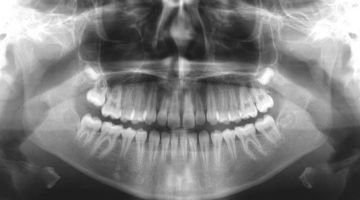

Read MoreDental X-ray

Dental X-rays are pivotal in contemporary dentistry, offering crucial insights into oral health. Leading the way in dental imaging in Delhi is the esteemed RECARVE MAXILLOFACIAL CENTRE & DENTAL STUDIO. Recognized for its proficiency in providing accurate and thorough dental diagnostics, the center plays a key role in advancing oral healthcare.